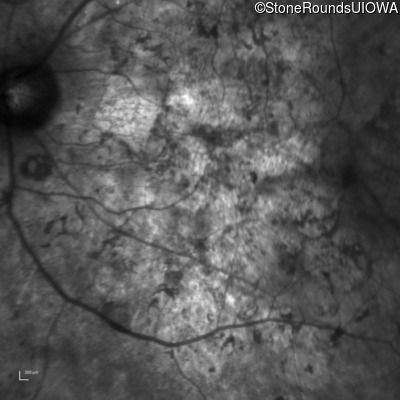

Infrared Fundus Photograph - Left - Hand Motion sc

Exemplar